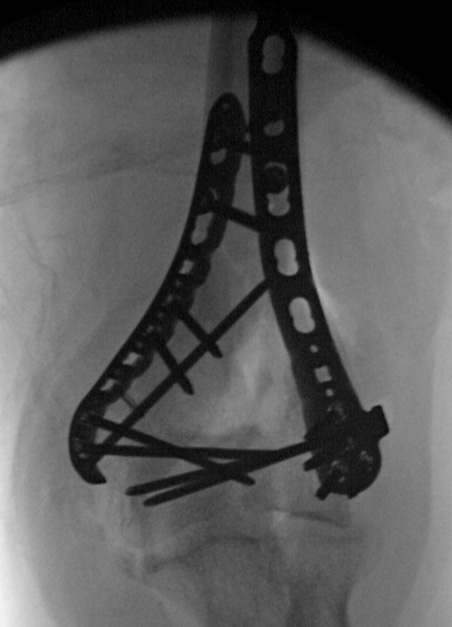

Intra-operative x-ray of a complex distal humerus fixation using two plates to stabilize the joint surface and both columns of the humerus